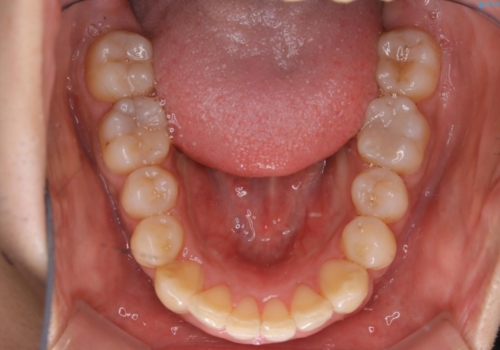

一見、表面はそこまで汚れが付着していないようにみえますが、裏面を見てみると、着色や歯石が多く付着していました。個人差はありますが、3カ月に1回の来院でもここまで汚れが付着する為、メンテナンスやクリーニングは、3ヶ月に1回をおすすめします。